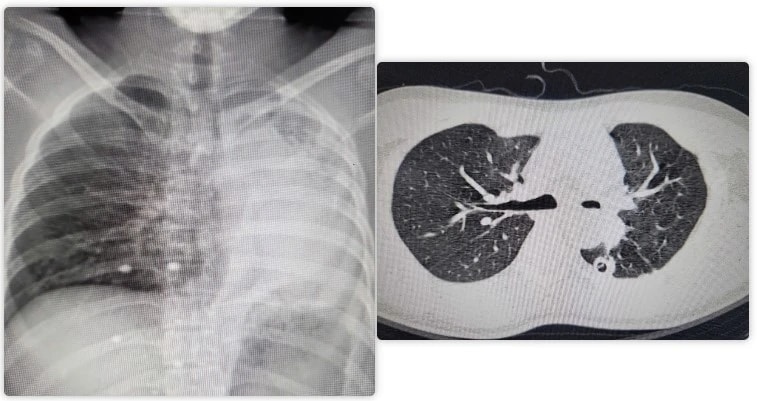

Phẫu thuật thành công hồi sinh lá phổi xẹp hoàn toàn cho nam bệnh nhân

Sau 4 giờ phẫu thuật cân não, các bác sĩ Bệnh viện Bạch Mai đã tái tạo thành công đường thở, giúp hồi sinh lá phổi xẹp hoàn toàn cho nam người bệnh bằng kỹ thuật nội soi tiên tiến.